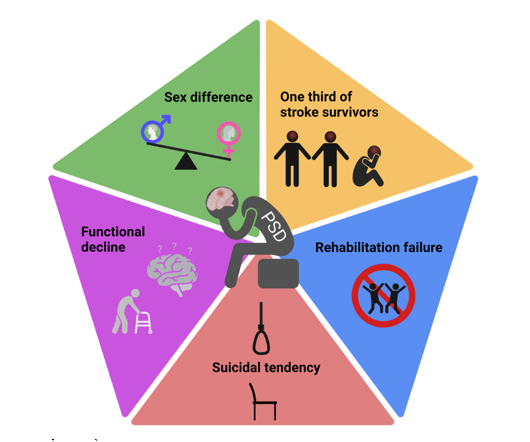

9 dấu hiệu trầm cảm của người bị đột quỵ

Nhiều bệnh nhân bị trầm cảm sau đột quỵ thường cảm thấy cô đơn, vô dụng và muốn tự tử. Bài viết của trang web Healthline sẽ nói rõ mối quan hệ của đột quỵ và trầm cảm cùng với cách vượt qua giúp bệnh nhân vượt qua nỗi mặc cảm nêu trên.